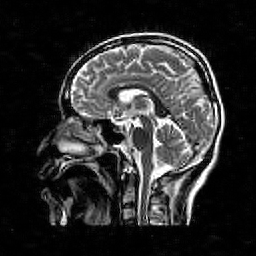

Hence both and should recover equally well. In the top row of Figure 1 we present the result of the flip test for a Gaussian random matrix. As is evident, the reconstructions and are comparable, thus indicating the RIP.

Having considered type II problems, let us now examine the flip test for a type I problem. As discussed, in applications such as MRI, X-ray CT, radio interferometry, etc, the matrix is imposed by the physical sensing device and arises from subsampling the rows of the DFT matrix .111In actual fact, the sensing device takes measurements of the continuous Fourier transform of a function . As discussed in BAACHGSCS ; BAGSAIEP , modelling continuous Fourier measurements as discrete Fourier measurements can lead to inferior reconstructions, and worse, inverse crimes. To avoid this, one must consider an infinite-dimensional compressed sensing approach, as in (2). See AHPRBreaking ; BAGSAIEP for details, as well as PruessmannUnserMRIFast for implementation in MRI. However, for simplicity, we shall continue to work with the finite-dimensional model in the remainder of this paper. Whilst one often has some freedom to choose which rows to sample (corresponding to selecting particular frequencies at which to take measurements), one cannot change the matrix .

It is well known that in order to ensure a good reconstruction, one cannot subsample the DFT uniformly at random (recall that the sparsifying transform is a wavelet basis), but rather one must sample randomly according to an appropriate nonuniform density AHPRBreaking ; Candes_Romberg ; Lustig ; WangAcre . See the bottom left panel of Figure 1 for an example of a typical density. As can be seen in the next panel, by doing so one achieves a great recovery. However, the result of the flip test in the bottom right panel clearly demonstrates that the matrix does not satisfy an RIP. In particular, the ordering of the wavelet coefficients plays a crucial role in the reconstruction quality. To explain this, and in particular, the high-quality reconstruction seen in the unflipped case, one evidently requires a new analytical framework.

Note that the flip test in Figure 1 also highlights another important phenomenon: namely, the effectiveness of the subsampling strategy depends on the sparsity structure of the image. In particular, two images with the same total sparsity (the original and the flipped ) result in wildly different errors when the same sampling pattern is used. Thus we conclude that there is no one optimal sampling strategy for all sparse vectors of wavelet coefficients.